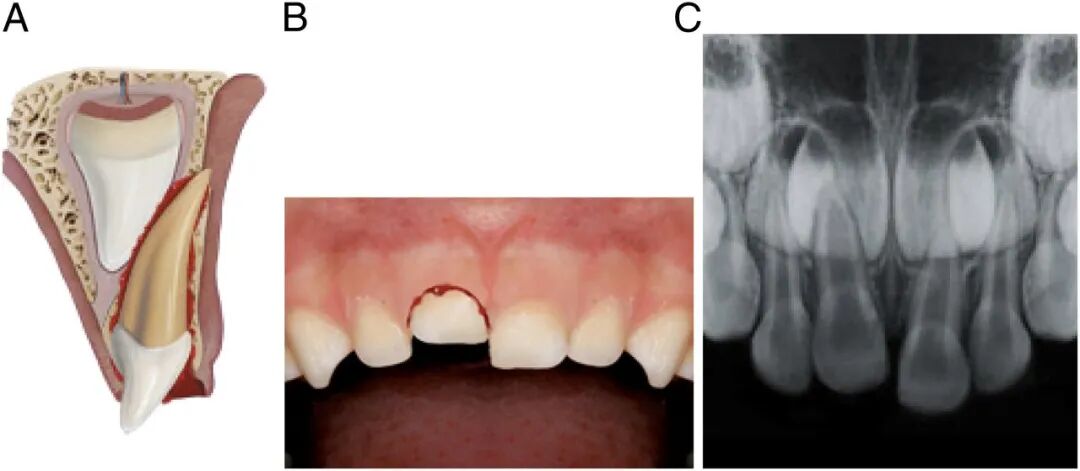

牙齿撕脱

科普推荐的泡牛奶啊、泡口水啊,都是针对恒牙的急救措施。

恒牙的撕脱是所有牙齿伤害中最严重的,而且首选治疗方法确实是立即再植。

为保证恒牙能成功接回去,磕掉牙第一时间家长应该这么做:

1、首先,先找到摔掉的牙,捏住牙冠部(注意不是牙根);

2、如果恒牙掉地上沾土了,千万别擦,在冷流动水下短暂冲洗10秒,然后重新放回牙槽中,再让孩子咬住干净棉球或毛巾将牙齿固定住,然后去急诊。

3、如果无法立即植入牙齿,则应将其存储在有助于保持牙周膜纤维细胞活力的介质中。比如泡在冷牛奶或生理盐水中,实在不行含在舌下,或者往杯子里吐口水,把牙齿泡进去也可以。

但是别把牙齿泡水里,因为水会引起牙周膜纤维细胞的渗透性溶解。

4、以上所有动作都要快,牙齿口外干燥超过60分钟,牙根细胞就不容易存活了。